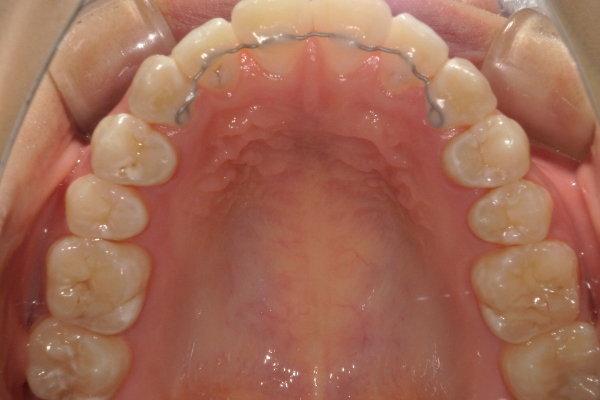

リンガルアーチ

細い弾線で歯を裏側から押すことで、1本〜数本の歯を傾斜移動させる装置です。 軽度の反対咬合や萌出位置の改善に用いられます。

ご自身では取り外しができず、通院時に調節を行うことで少しずつ歯を動かします。

リンガルアーチ単体で使用することもありますし、ワイヤー矯正やフェイシャルマスク等と併用することも多いです。